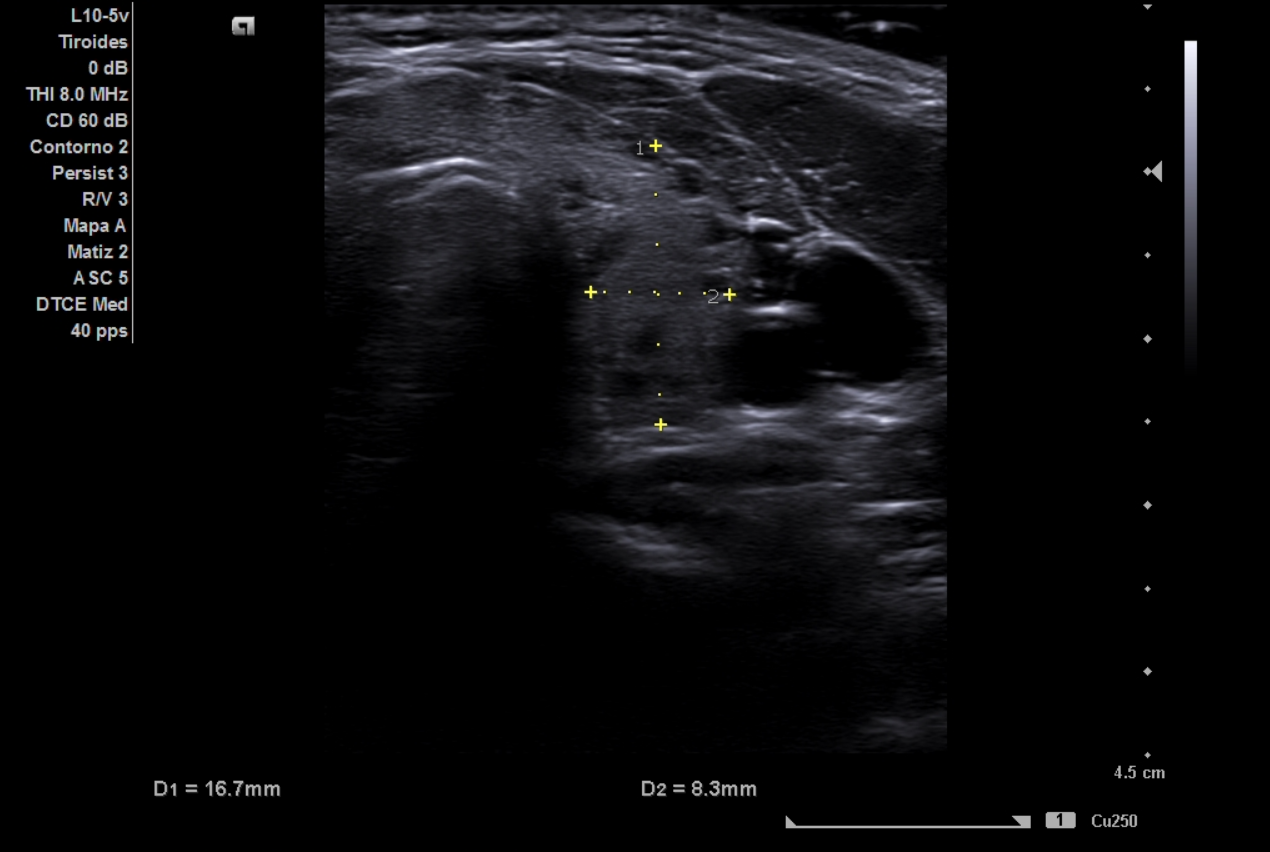

La ecografía clínica de tiroides muestra lóbulo derecho de 18 mm y lóbulo izquierdo de 16,7 mm en eje anteroposterior, con ecoestructura hipoecoica y heterogénea, presencia de múltiples quistes anecoicos milimétricos y un discreto aumento de la vascularización. No se identifican nódulos sólidos. El Doppler registra un pico sistólico máximo de 23 cm/s en ambas arterias tiroideas inferiores. Estos hallazgos son compatibles con tiroiditis.